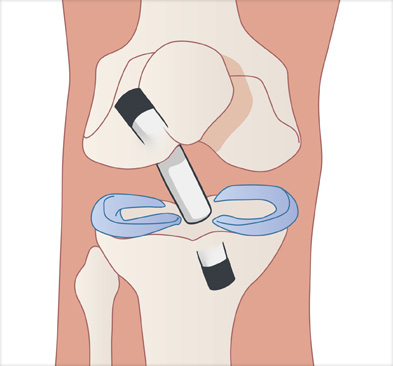

십자인대 재건술은 손상된 인대를 자가건이나 타가건을 활용해 원래의 인대의 위치에 재건하여 무릎의 기능을 회복시킵니다.

경골과 대퇴골 사이에 남아 있는 전방십자인대 제거

이식할 인대 삽입

이식한 인대 고정